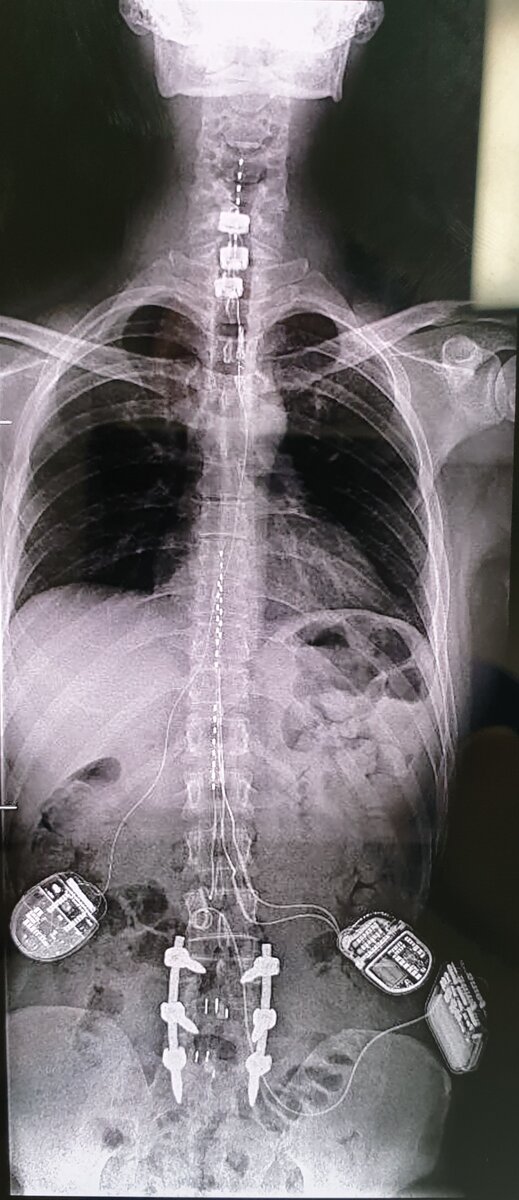

В мире более 8 миллионов людей с имплантированным кардиостимулятором, еще у нескольких миллионов инсулиновые помпы, центральные и периферические нейростимуляторы. В соответствии с определением, все они киборги. О последних сегодня и поговорим. А помогут нам в этом Анна Гофман - старший лаборант НИИ Клинической хирургии и пациент, который был у меня на приеме на последнем дежурстве. Вот его рентген:

Рентген пациента N, - киборга.

Видите эти схемы с проводами, идущими к позвоночнику? Это нейростимуляторы, которые передают электрический импульс на нейроны.

Пациент, чей рентген на заглавной фотографии - военный журналист. Вы его знаете, это довольно одиозная фигура. Он на протяжении 8 лет после травмы может передвигаться и контролировать тазовые органы благодаря нейростимуляторам. В верхней части спинного мозга происходит регистрация импульса, который передается в нижнюю, минуя поврежденный участок. Железный человек. Во всех смыслах.